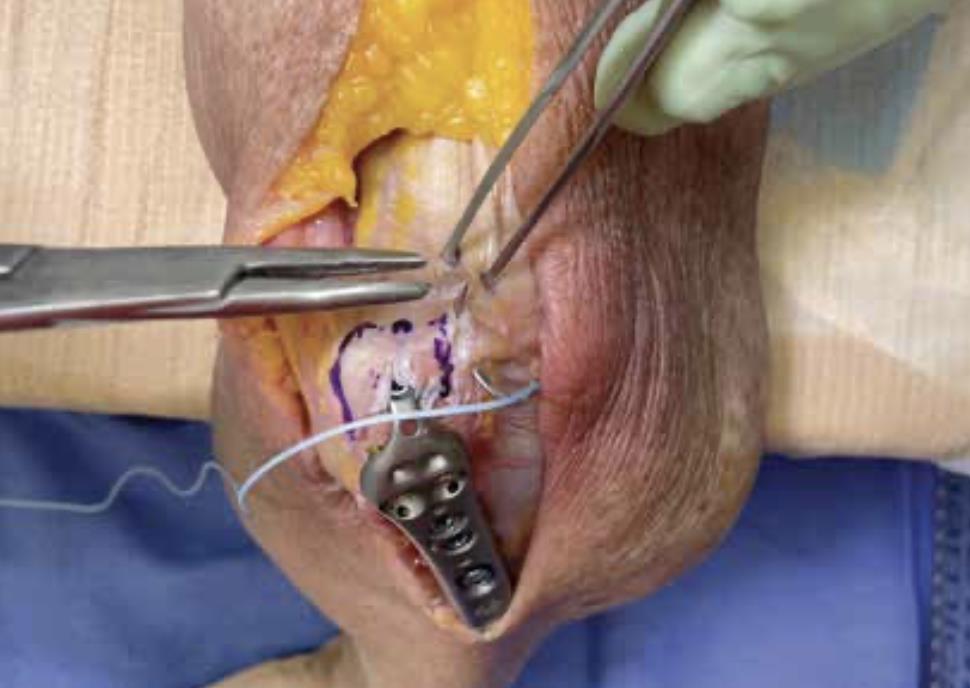

• Begin Passing Suture

• with the elbow in 90° flexion, mark a spot approximately 5mm distal to the home run tab

• Outline Suture Path

• draw an outline as shown to mark the suture path

• note: make sure the suture path goes through the medial head of the triceps tendon

• begin a non-locked running stitch along the lateral side

• pass the suture deep to capture as much of the underlying tissue as possible